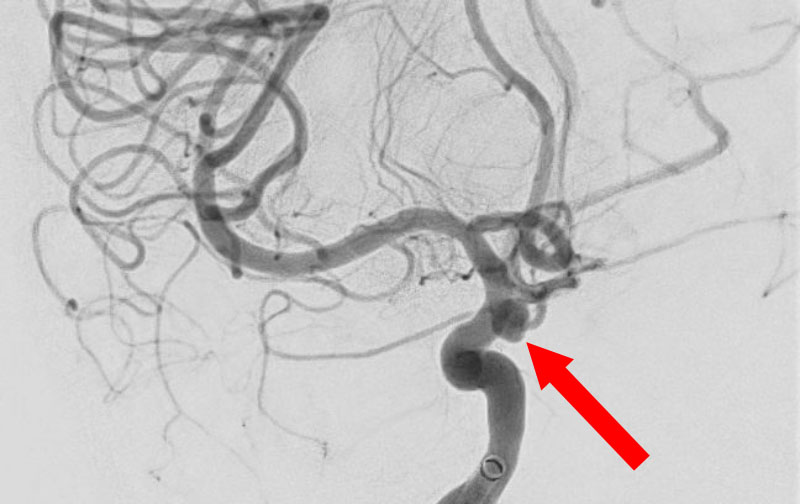

'26年4月

左椎骨動脈後下小脳動脈分岐部動脈瘤

70代

院内外来

No.1628 手術前